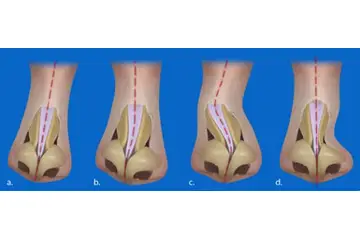

Kıkırdak Doku Çeşitleri Kıkırdak doku, bağ dokuları arasında yer alan, esnek ve dayanıklı bir yapıya sahip olan dokulardır. Farklı türleri ve işlevleri, vücudun çeşitli bölgelerinde önemli roller üstlenmektedir. Bu makalede, kıkırdak dokunun çeşitleri ve özellikleri detaylı bir şekilde ele alınacaktır. Kıkırdak Doku Türleri Kıkırdak doku üç ana türde sınıflandırılmaktadır: hyalin kıkırdak, elastik kıkırdak ve fibröz kıkırdak. Her bir tür, farklı yapısal özelliklere ve işlevsel amaçlara sahiptir.

Kıkırdak Dokunun Özellikleri Kıkırdak dokunun bazı ayırt edici özellikleri şunlardır:

Kıkırdak Doku ve Hastalıklar Kıkırdak dokunun sağlık durumu, birçok hastalığın gelişiminde önemli bir rol oynamaktadır. Osteoartrit gibi dejeneratif hastalıklar, kıkırdak dokusunun bozulmasıyla ilişkilidir. Ayrıca, kıkırdak dokunun yaralanmaları, spor yaralanmaları ve travmalar sonucunda meydana gelebilmektedir. Kıkırdak Doku Araştırmaları ve Gelecek Perspektifleri Günümüzde kıkırdak doku araştırmaları, doku mühendisliği ve yenileyici tıp alanında yoğunlaşmaktadır. Kıkırdak hasarını onarmak veya yeniden oluşturmak amacıyla hücresel tedavi yöntemleri ve biyomühendislik uygulamaları geliştirilmektedir. Bu alandaki ilerlemeler, kıkırdak ile ilgili hastalıkların tedavisinde önemli yenilikler getirebilir. Sonuç olarak, kıkırdak doku, vücutta önemli bir rol oynamakta olup, farklı türleriyle birlikte çeşitli işlevler üstlenmektedir. Bu yapıların sağlığı, genel sağlık durumu üzerinde önemli bir etkiye sahiptir ve araştırmalar bu alanda devam etmektedir. |